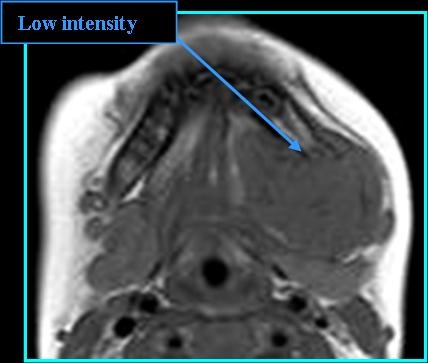

Radiologic Findings

- On MR: On T1 low to intermediate intensity when compared to muscle, on T2 heterogeneous signal, on T1 post-contrast mild to moderate enhancement